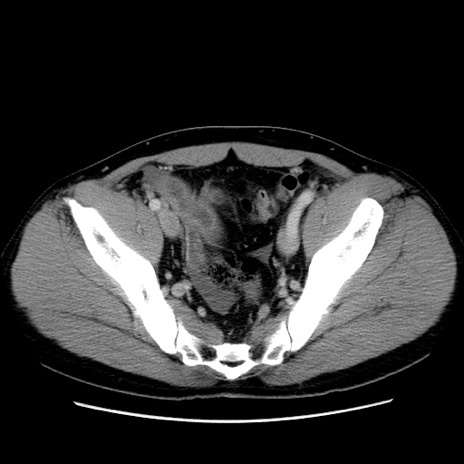

症例4(横断像)

【症例】30歳代男性

【主訴】腹痛、嘔吐

【現病歴】昨晩から突然の腹痛あり、その後嘔吐、軟便も出現。腹痛が改善しないため救急搬送となる。2日前にしめ鯖の食事歴あり。

【身体所見】意識清明、苦悶様、BP 135/90mmHg、BT 35.7℃、腹部:平坦、やや硬、心窩部〜臍部に自発痛、圧痛あり、筋性防御+、反跳痛-

【データ】WBC 8100、CRP 0.57